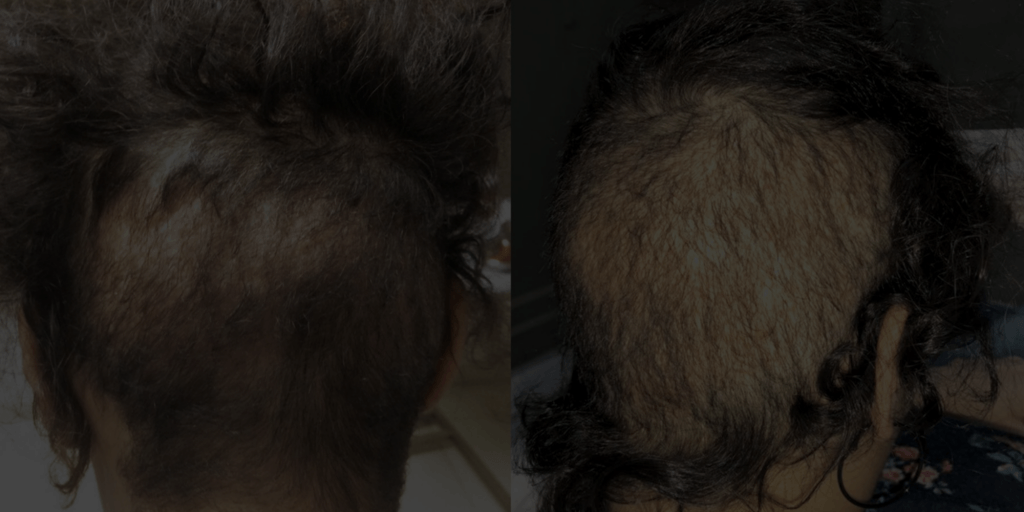

돌이킬 수 없는

결과

불법 진료소에 가면 무슨 일이 일어날 수 있나요?

| 끔찍한 감염 | 생명을 위협하는 합병증 | 끔찍한 결과 |